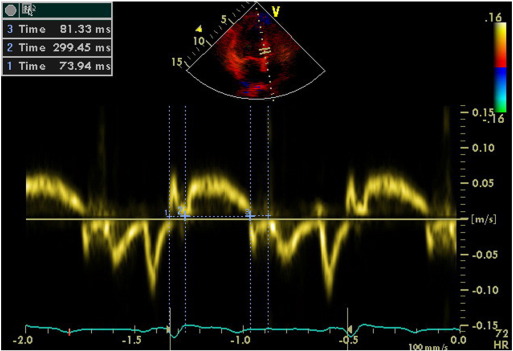

We calculated TDI-derived regional MPI using the values of both systolic and diastolic parameters at LV septal base (Fig. 3), then lateral base and found that MPI values were significantly abnormal at both region in group II compared with those in group I and group III (both p < 0.0001, Table 3). However, despite abnormal MPI in both hypertrophied LV walls, septal MPI was more severely impaired compared with that of lateral MPI in group II (p = 0.012). Septal MPI was correlated moderately with septal wall thickness (r = 0.447, p < 0.001, Fig. 4).

Evaluation of isovolumetric contraction time, contraction time and isovolumetric ...

Fig. 3.

Evaluation of isovolumetric contraction time, contraction time and isovolumetric relaxation time of the LV septal base by tissue Doppler imaging in a hypertensive patient with left ventricular hypertrophy (MPI = 62).